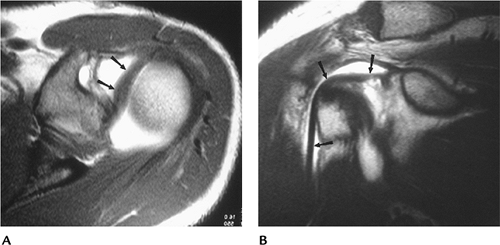

![]() |

FIGURE 7-29

P.484

FIGURE 7-30